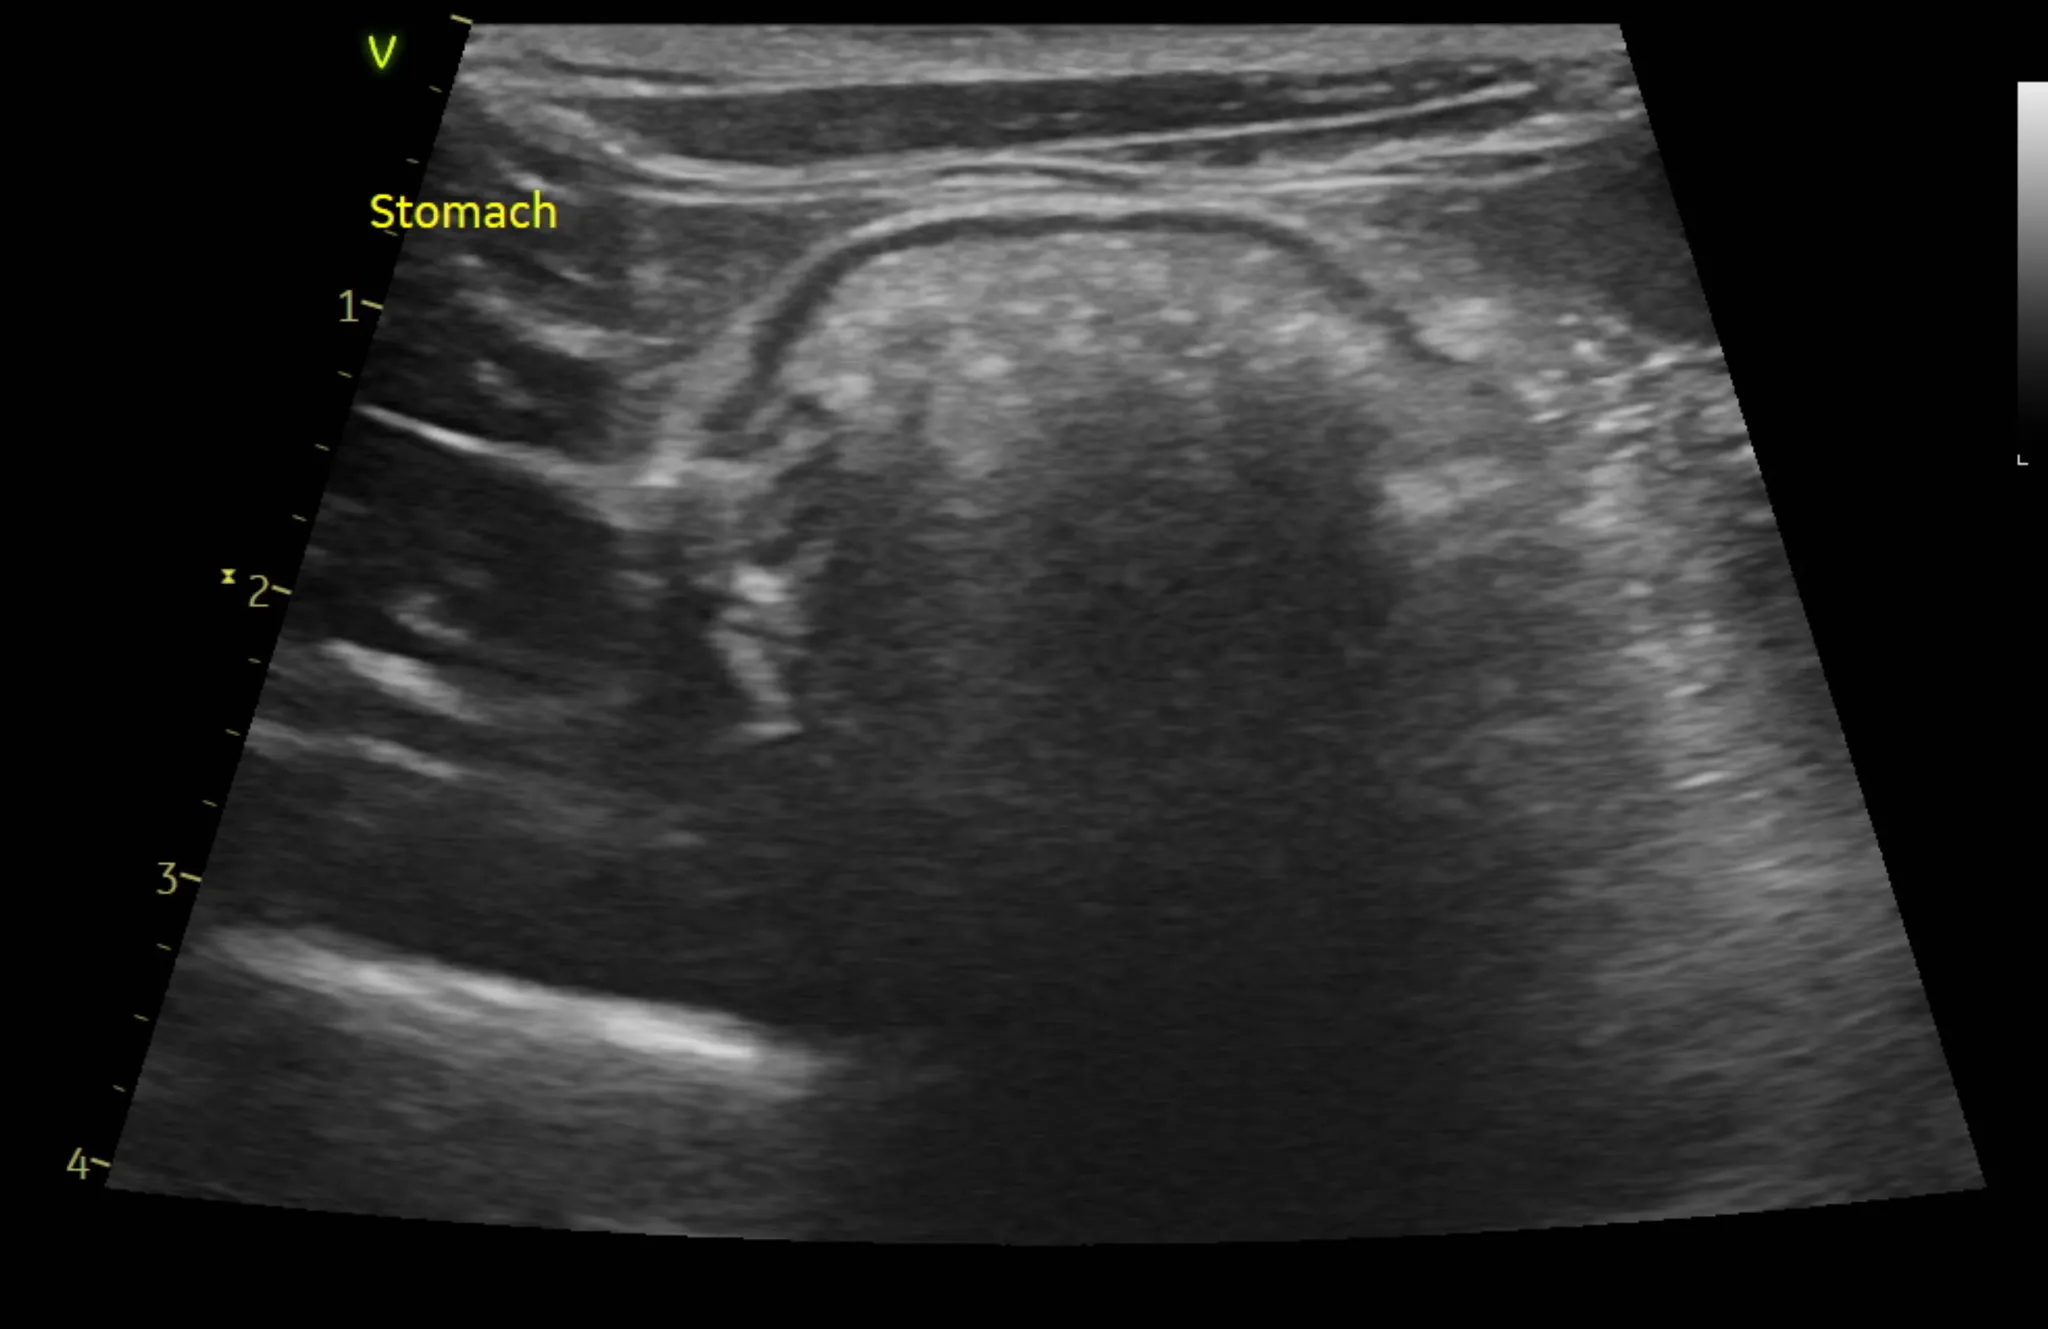

3. 복부 초음파 검사 결과

복부 초음파 검사로는 간, 신장 등 복부 장기의 모양과 결석, 종양등의 이상여부를 알 수 있습니다.

또한 방광 결석, 다낭포성 신장질환 같은 고양이에서 잘 생기는 질환의 경우 초음파 검사로만 알 수 있으므로 매우 중요한 검사 중 하나입니다.

복부 초음파 검사 상 특이사항은 발견되지 않았습니다.

1년 주기로 검사를 추천드립니다.